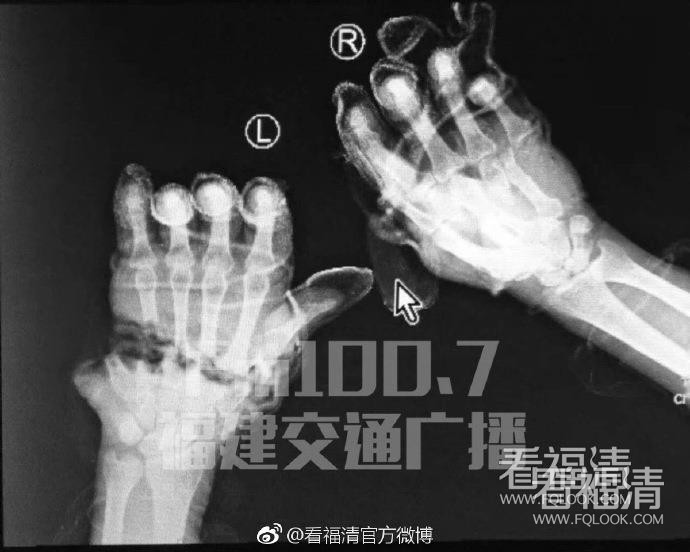

福清一男子双手被切断,9名医生轮番接力22小时接断掌!

4月30号下午,在福清一家居用品公司上班的张师傅,一双手掌竟被齐齐切断!当时,张师傅正在操作冲床,将材料送到里面压模,按照设计,冲床有红外感应,人手在里面的话,是不可能工作的。但由于已经连续上班比较长时间,迷糊间,张师傅在操作机器时忘记把红外开关打开,导致自己的双掌,被力量达60吨的冲床直接切断。事故发生后,厂里立即派人将张师傅送到武警福建总队医院显微外科救治,急诊科、麻醉科、放射科、显微外科医护人员放弃节假日休息时间,紧急动员,历经22小时,进行了超长时间的显微手术,断掌终于被接上。